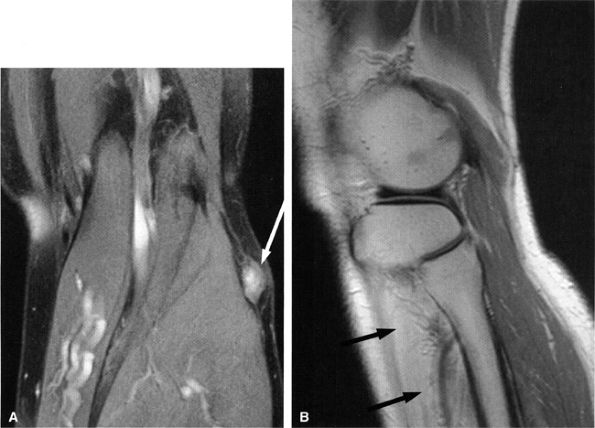

FIGURE 6.29 ● Common peroneal neuropathy secondary to a nerve sheath tumor. (A) Coronal T2-weighted fat-suppressed image demonstrating a nerve sheath tumor of the common peroneal nerve (arrow). (B) Sagittal T1-weighted image showing denervation atrophy of the anterior tibial muscle (arrows).

FIGURE 6.31 ● Surgically proven common peroneal neuropathy and denervation secondary to a hypertrophied biceps femoris muscle. (A) Axial T1-weighted image showing the common peroneal nerve (arrow) entrapped between a hypertrophied short head of the biceps femoris muscle (white asterisk) and the lateral head of the gastrocnemius muscle (black asterisk). (B) Axial T2-weighted fat-suppressed image displaying denervation edema in the anterolateral compartment muscles (arrows).